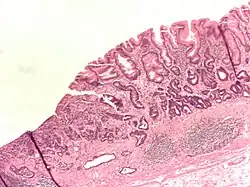

- Gastric adenocarcinoma is a malignant epithelial tumour, originating from glandular epithelium of the gastric mucosa. Stomach cancers are about 90% adenocarcinomas.[65] Histologically, there are two major types of gastric adenocarcinoma (Lauren classification): intestinal type or diffuse type. Adenocarcinomas tend to aggressively invade the gastric wall, infiltrating the muscularis mucosae, the submucosa, and then the muscularis propria. Intestinal-type adenocarcinoma tumour cells describe irregular tubular structures, harbouring pluristratification, multiple lumens, and reduced stroma ("back to back" aspect). Often, it is associated with intestinal metaplasia in neighbouring mucosa. Depending on glandular architecture, cellular pleomorphism, and mucosecretion, adenocarcinoma may present 3 degrees of differentiation: well, moderate, and poorly differentiated. Diffuse type adenocarcinoma (mucinous, colloid, linitis plastica or leather-bottle stomach) tumour cells are discohesive and secrete mucus, which is delivered in the interstitium, producing large pools of mucus/colloid (optically "empty" spaces). It is poorly differentiated. In signet ring cell carcinomas, the mucus remains inside the tumour cell and pushes the nucleus to the periphery, giving rise to signet-ring cells.

Poor to moderately differentiated adenocarcinoma of the stomach. H&E stain.

Adenocarcinoma of the stomach and intestinal metaplasia. H&E stain.